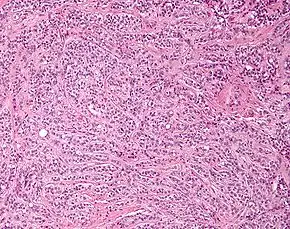

| Micrograph of a Sertoli cell tumour. H&E stain. | |